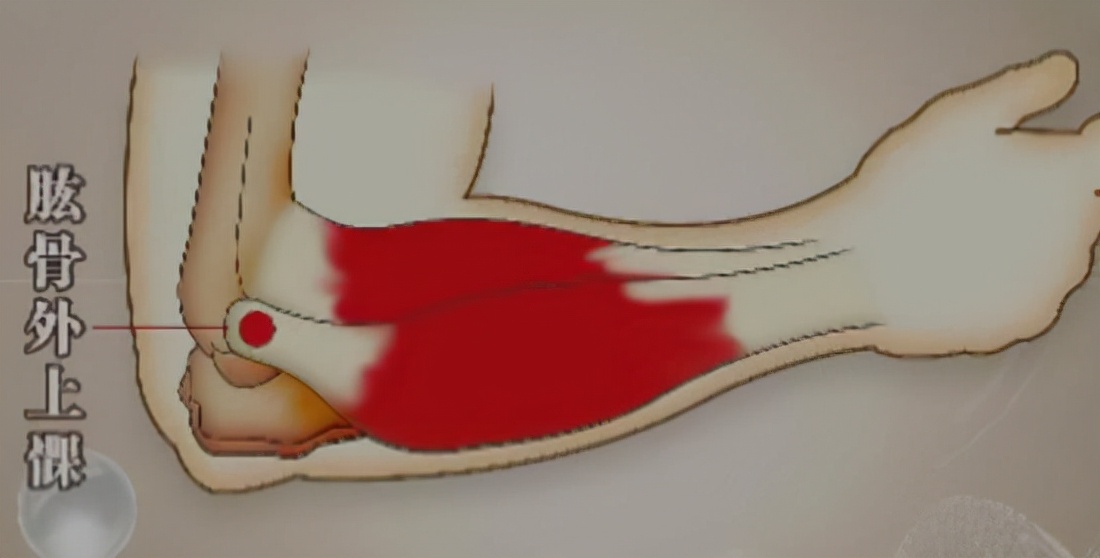

网球肘即肱骨外上髁炎,因伸腕肌肌腱反复损伤并自我修复的双重作用,造成的肌腱纤维化、无菌性炎症、活动受限、疼痛、肌肉萎缩等疾症。一般情况下,通过休息、物理治疗,以及牵拉、离心力量训练等运动疗法的治疗,可以在较短时间内获得痊愈;即便情况比较严重,通过积极的康复治疗也可在1年左右重返正常的工作和运动。但如果是积重难返的、存在严重纤维化和钙化的“网球肘”,就要考虑采用外科手术的方法进行治疗。